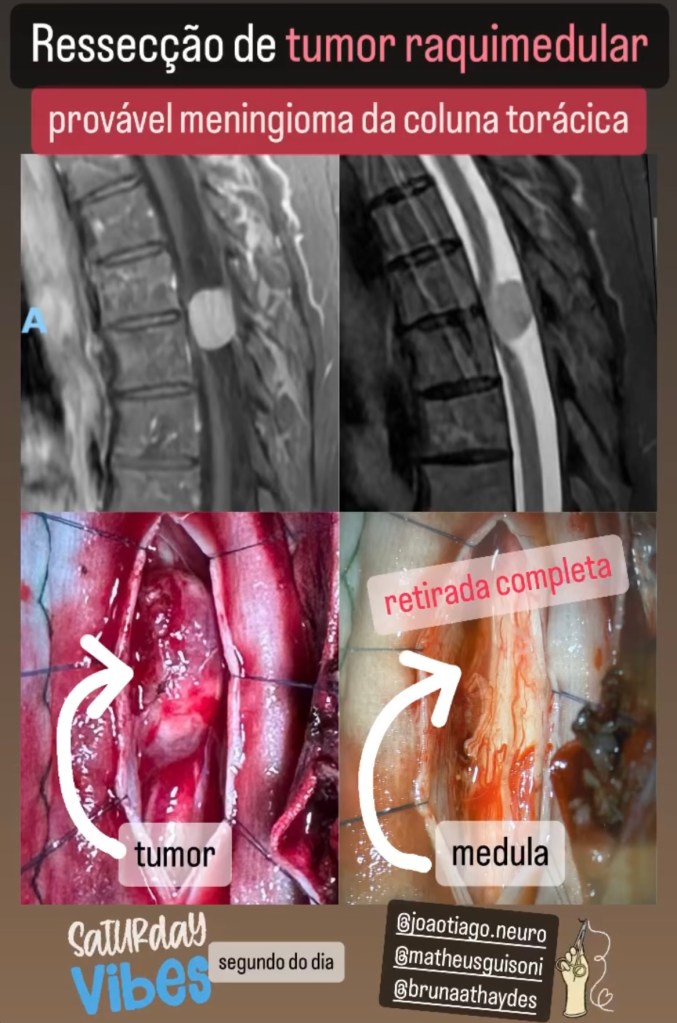

GALERIA De cirurgias

Abaixo você pode conferir imagens de algumas cirurgias já realizadas por Dr. Marcelo Camargos. Caso tenha alguma dúvida ou interesse, não deixe de fazer contato para maiores esclarecimentos!